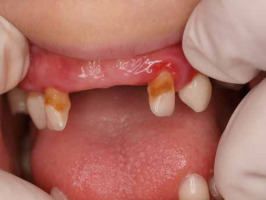

When he was 5 years of age the intraoral examination revealed incomplete primary dentition with five missing teeth, marginal gingivitis, interdental papilla hypertrophy, carious lesions in seven primary teeth, and one permanent tooth of various degrees of advancement for conservative treatment (Fig. 1). The patient was qualified for simultaneous dental treatment under general anesthesia. A panoramic radiograph picture was taken showing the advanced destruction of the alveolar bone in the maxilla and the alveolar part of the mandible. Three primary teeth were completely devoid of bone base. The roots of the lower incisors were only half of their normal length (Fig. 2). Under antibiotic protection (amoxicillin with clavulanic acid at a dose of 30 mg/kg), professional removal of dental plaque and conservative treatment of teeth extraction of four primary teeth with complicated caries and periodontitis were performed. The patient was provided with permanent dental care.